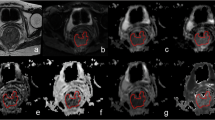

As illustrated in Table 4 and Fig. 4, the difference in AUC between the ADC ratio and ADCpmean was not significant in distinguishing tumor differentiation (AUC, 0.700 vs. 0.664, p = 0.336). The AUCs of 0.707, 0.663, 0.622, and 0.614 for the ADC ratio, ADCpmean, ADCtmean, and ADCtmin were not significantly different from each other in distinguishing T classification (p = 0.098–0.586). The AUC was greater for the ADC ratio than for the ADCtmean (0.776 vs. 0.621, p = 0.001) for predicting LNM. However, the AUC for ADC ratio was not significantly greater than either ADCtmin (0.776 vs. 0.697, p = 0.115) or ADCpmean (0.776 vs. 0.748, p = 0.320) for predicting LNM. The AUCs of 0.686, 0.677, and 0.625 for ADCpmean, ADC ratio, and ADCtmin were not significantly different from each other for assessing ENE (p = 0.420–0.782). For predicting TD and LVI, the AUC for ADC ratio was significantly better compared with either ADCtmin (0.848 vs. 0.635, p < 0.001; 0.778 vs. 0.656, p = 0.004, respectively) or ADCtmean (0.848 vs. 0.682, p < 0.001; 0.778 vs. 0.636, p = 0.002, respectively), but there were no significant differences between ADC ratio and ADCpmean (0.848 vs. 0.819, p = 0.362; 0.778 vs. 0.735, p = 0.245, respectively).

Receiver operating characteristic curves. A Differentiation of well–moderate from poor differentiation with ADCpmean (blue line) and ADCpmean/ADCtmean (ADC ratio) (red line). B Differentiation of T1–2 from T3–4 with minimum values of tumor ADC (ADCtmin) (yellow line), ADCtmean (purple line), ADCpmean (blue line), and ADC ratio (red line). C Differentiation of lymph node metastasis (LNM)-negative from LNM-positive with ADCtmin (yellow line), ADCtmean (purple line), ADCpmean (blue line), and ADC ratio (red line). D Differentiation of extranodal extension (ENE)–negative from ENE-positive with ADCtmin (yellow line), ADCpmean (blue line), and ADC ratio (red line). E Differentiation of tumor deposit (TD)–negative from TD-positive with ADCtmin (yellow line), ADCtmean (purple line), ADCpmean (blue line), and ADC ratio (red line). F Differentiation of lymphovascular invasion (LVI)–negative from LVI-positive with ADCtmin (yellow line), ADCtmean (purple line), ADCpmean (blue line) and ADC ratio (red line)